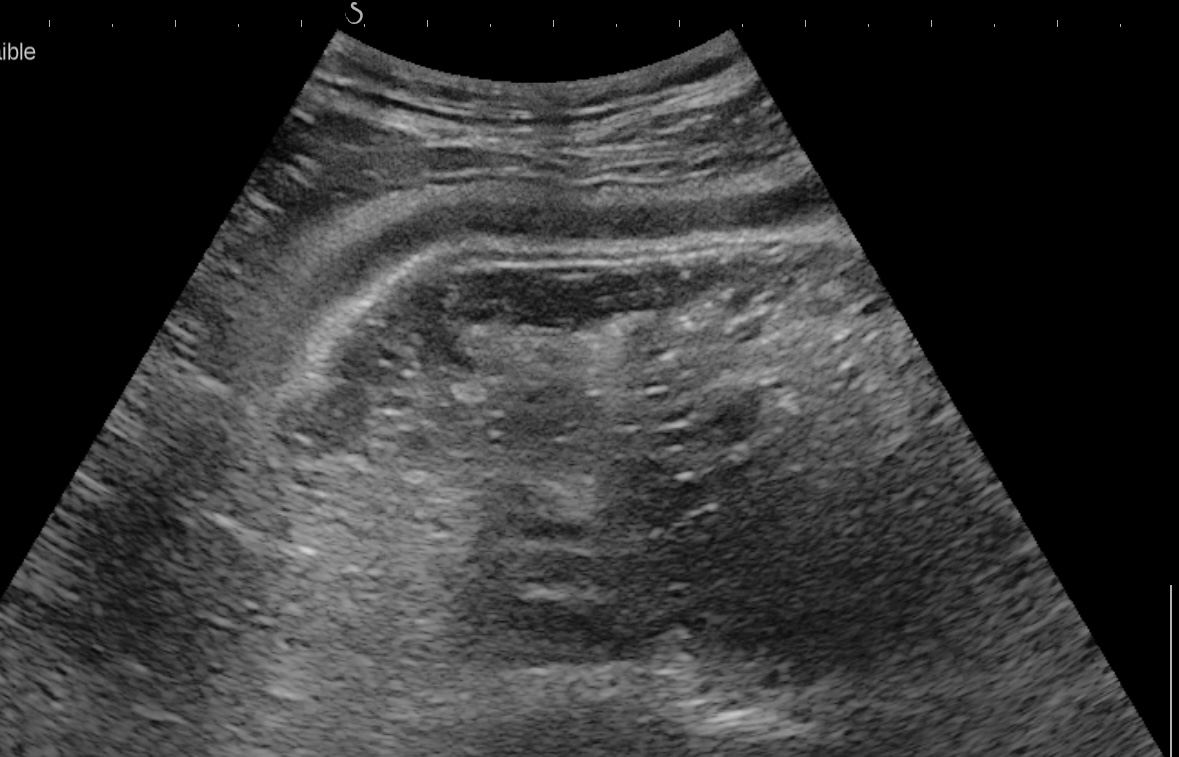

Sigmoïde basse fréquence

Même lésions avec la sonde haute fréquence, épasissement de 7 mm prédominant à la 3 ième couche, c'est à dire la sous muqueuse, hyperéchogène

Ici score de Milan = (1,4 x7+2)=11,8 maladie très active.